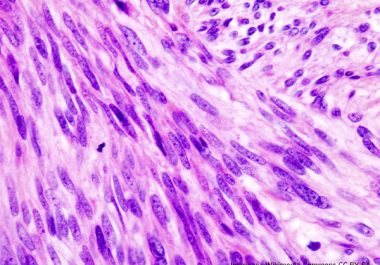

The FDA approved a combination of two immune checkpoint inhibitors to treat adult patients with unresectable malignant pleural mesothelioma....